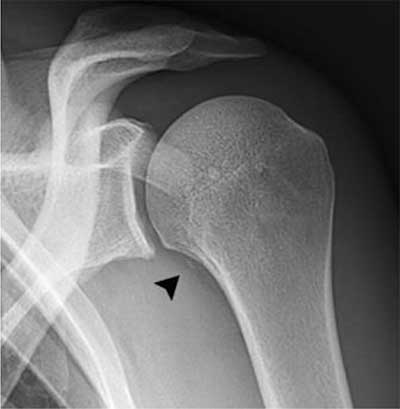

Figure 1

A 29-year-old rugby player presenting after shoulder trauma. Standard radiography of the left shoulder. A small fleck of bone (black arrowhead) is seen medial to the proximal humerus.